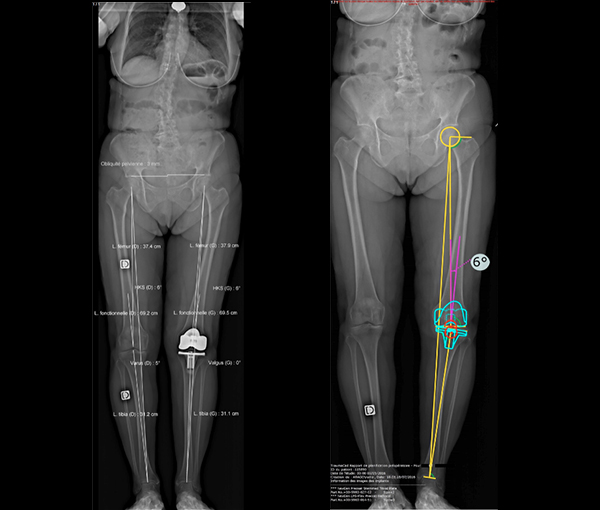

EOS permet l’étude des déformations de la colonne vertébrale et/ou des membres inférieurs (notamment des articulations des hanches et des genoux), en apportant une précision et des informations fonctionnelles jusqu’ici indisponibles en routine.

Dans la prise en charge des prothèses, il permet d’améliorer la planification informatisée préopératoire, de contrôler la bonne exécution chirurgicale de la planification et la bonne correction des déformations.